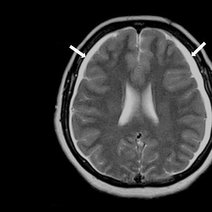

血管源性脑水肿的基本发病机制是微血管通透性增高.正常血脑屏障只容许一些小分子溶质通过,因脑毛细血管通透性很低,基外周几乎被星形胶质细胞终足所包围,后者被视为血脑屏障的组成部分(第...

脑水肿是脑内水分异常增多致脑容积增大源于液体平衡失衡,血脑屏障受损等引发血管源性脑水肿(多由脑肿瘤、脑外伤等致血脑屏障破坏,病变在白质范围较广),脑缺血缺...